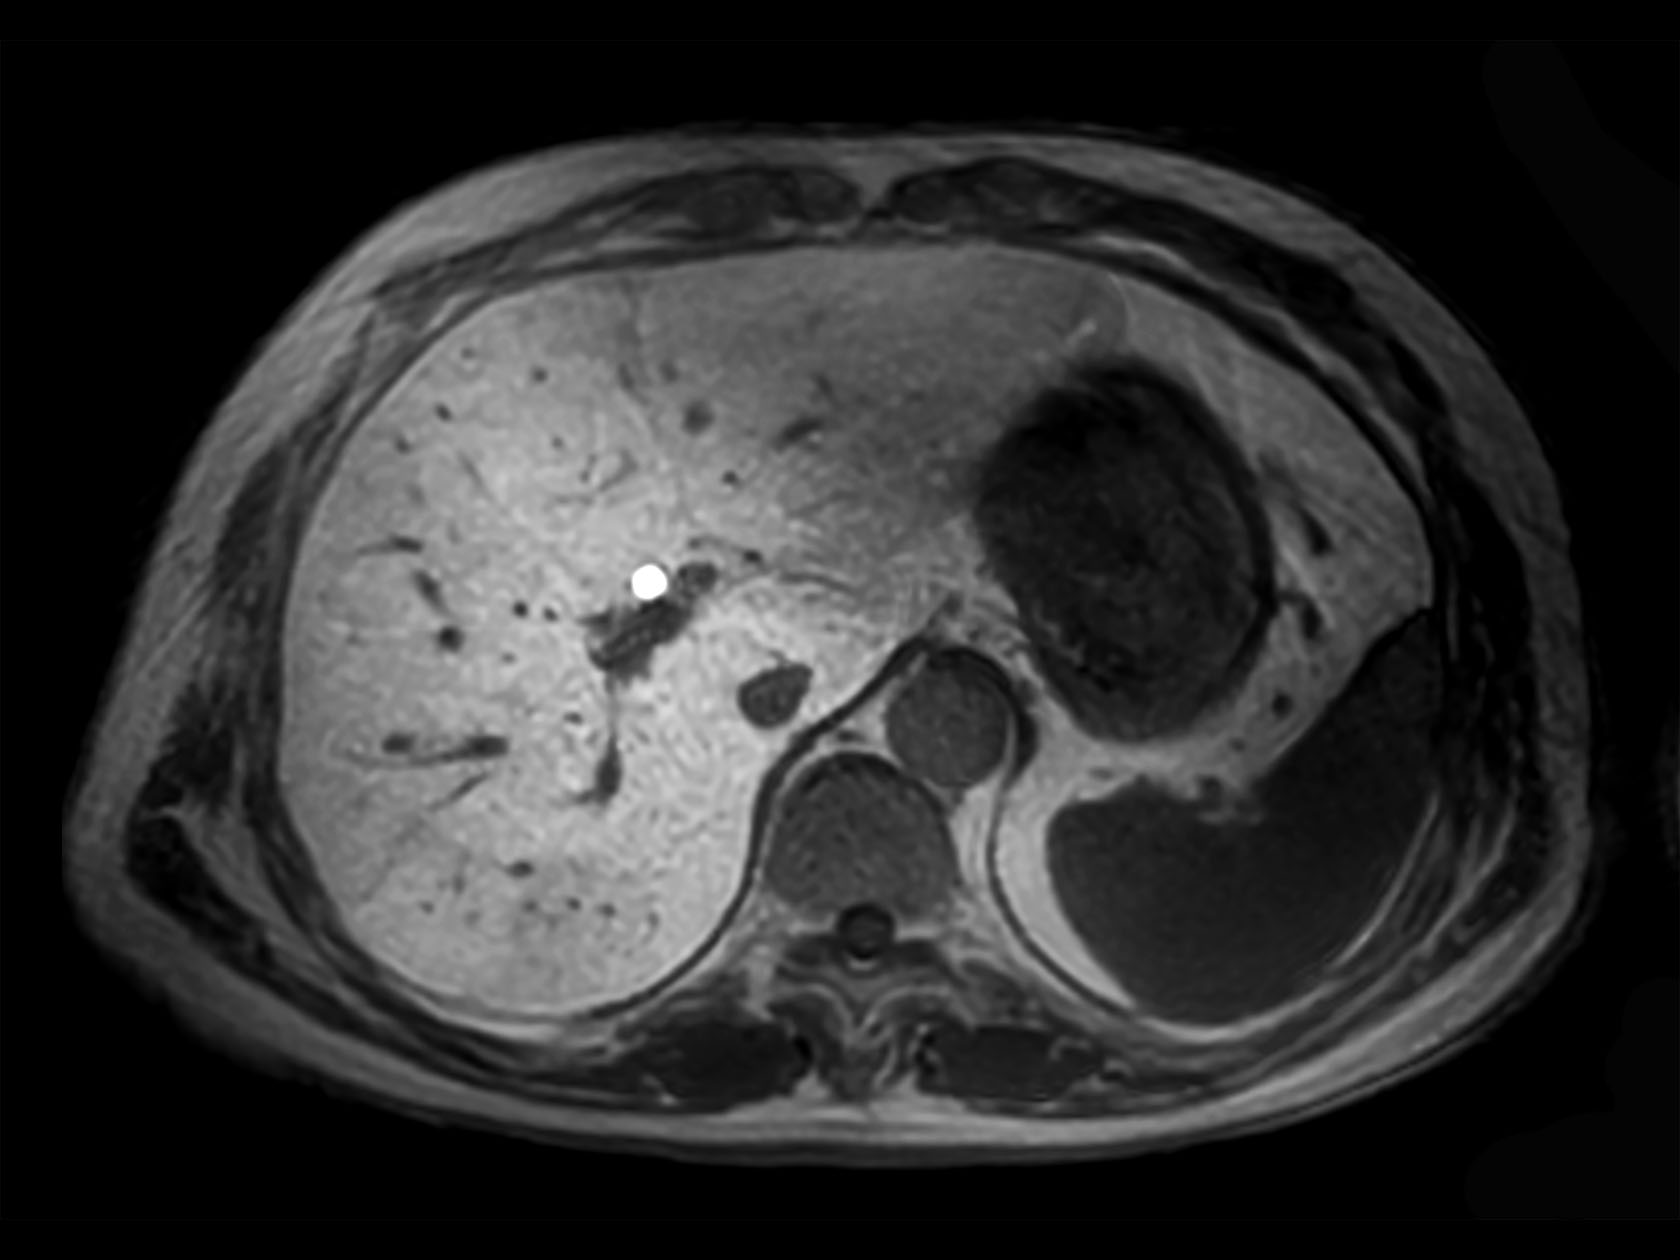

Axial eTHRIVE